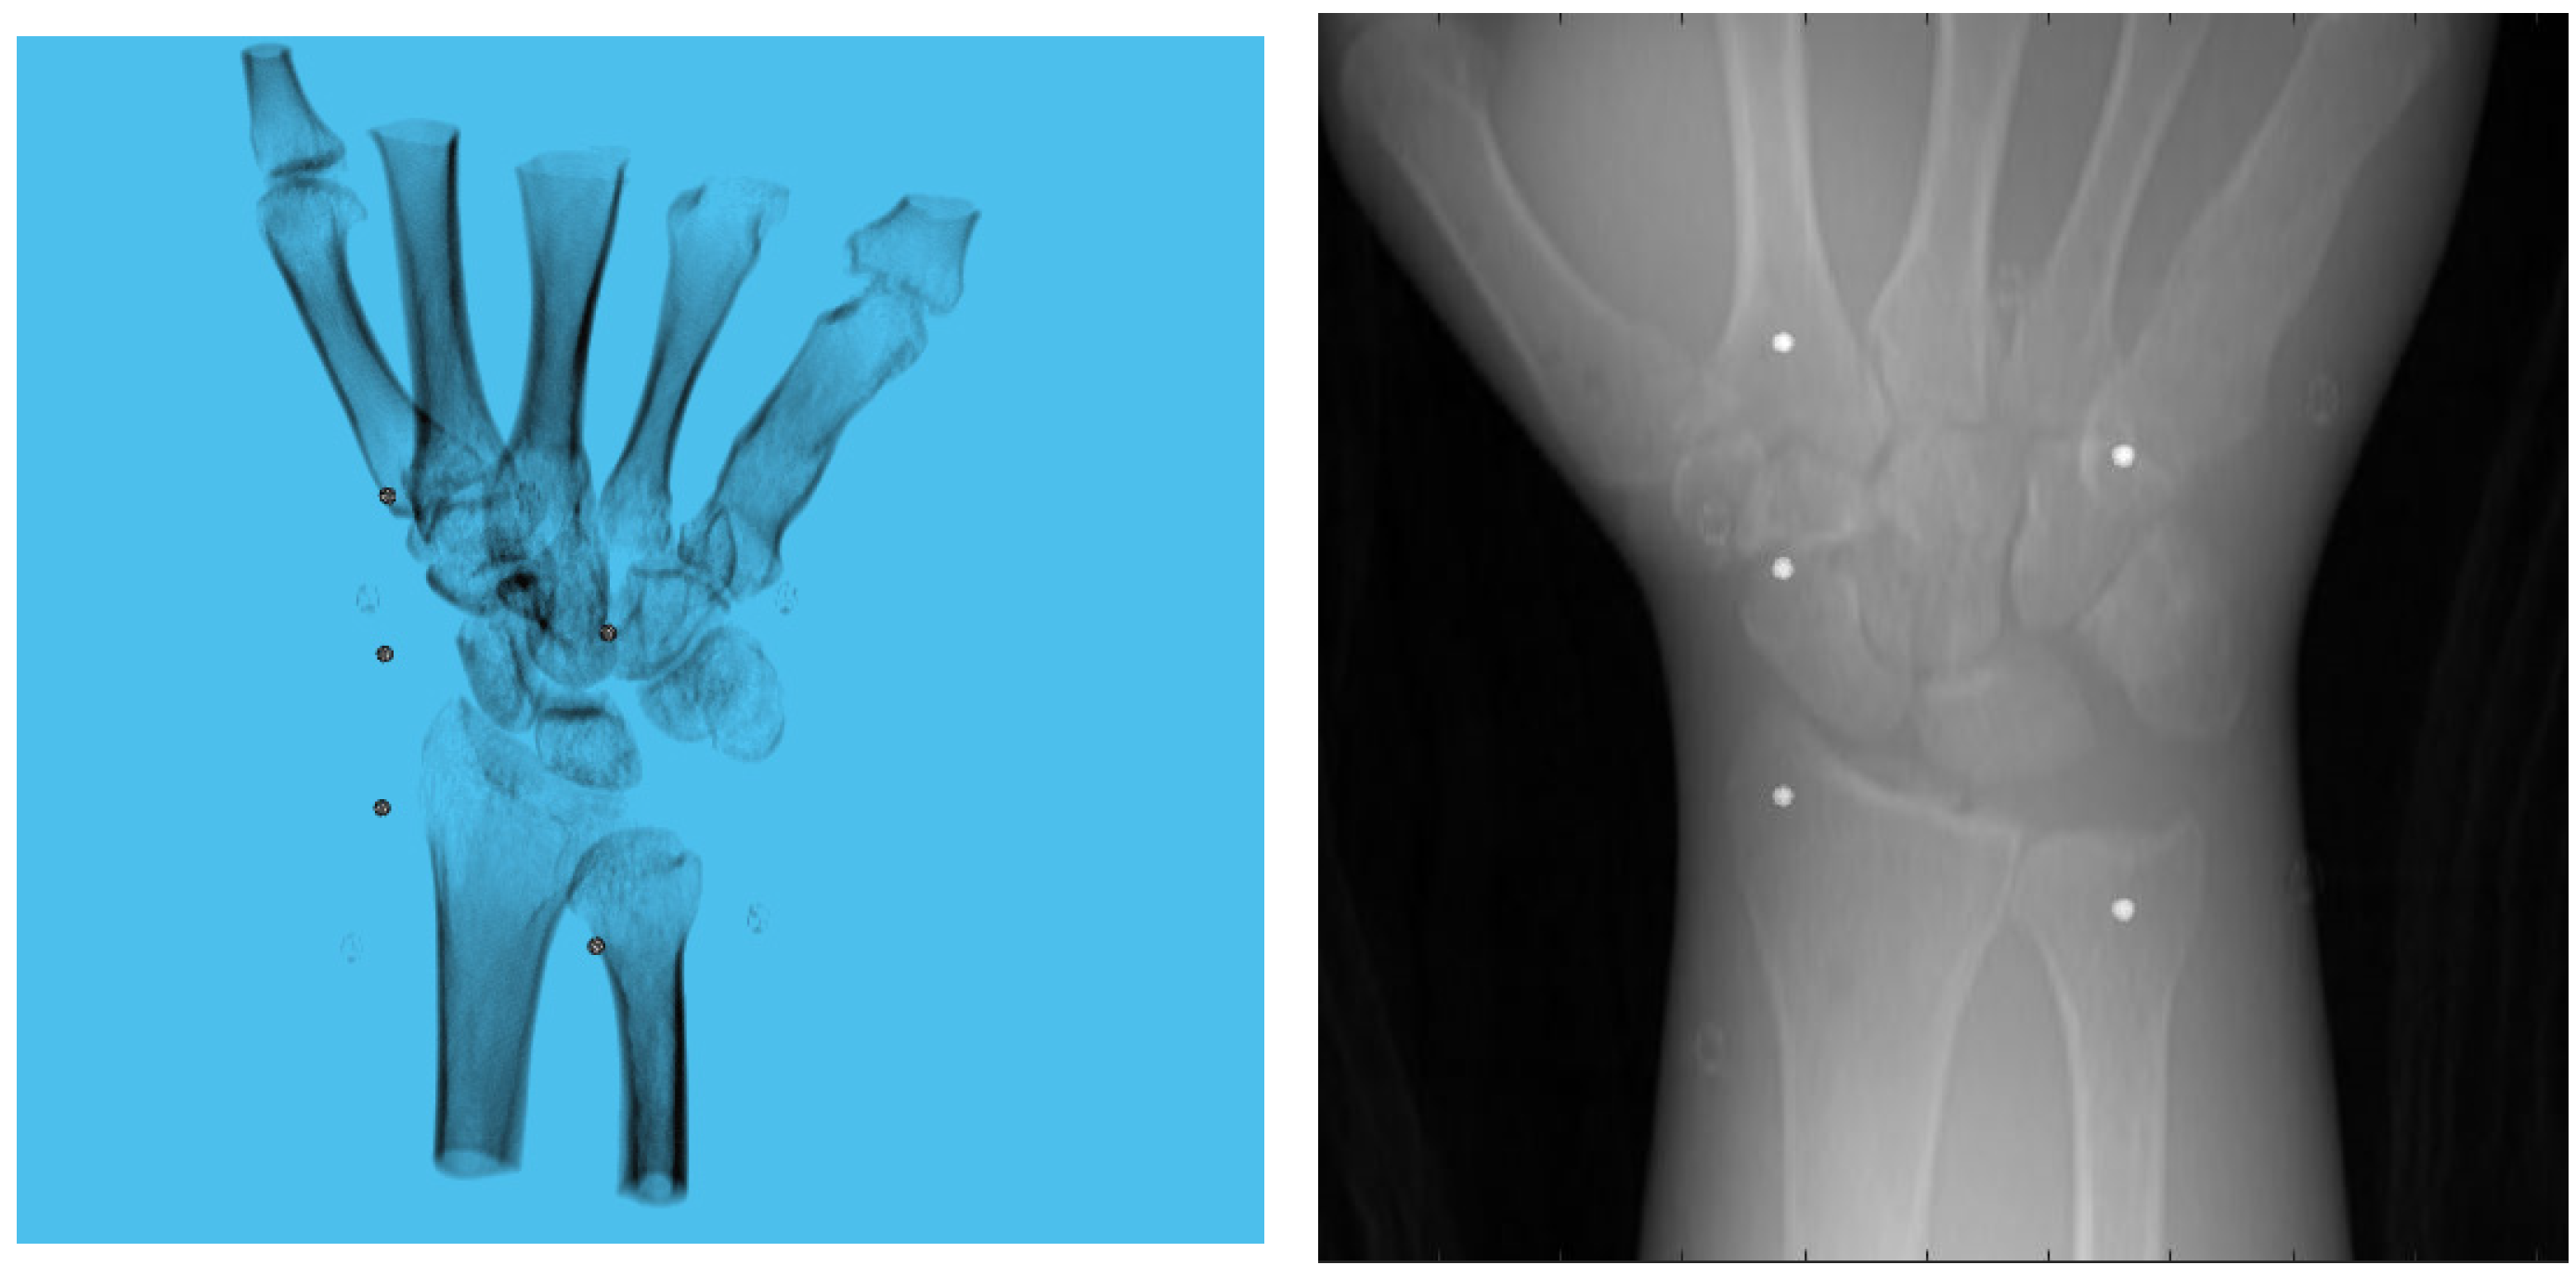

2.1. C-Arm Calibration

2.2. Pose Estimation

3.1. Simulation Setup